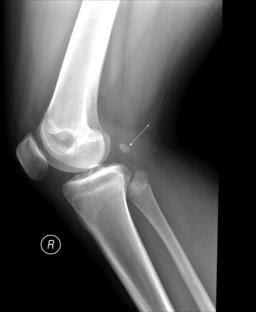

What is a Fabella?

A sesamoid bone located in the lateral head of the gastrocnemius muscle, behind the lateral femoral condyle.